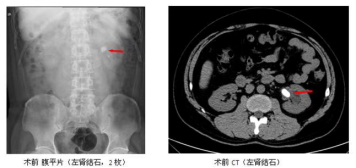

經(jīng)皮腎鏡碎石術(shù)是將腎鏡通過皮腎通道(一條經(jīng)皮膚穿入腎盂腎盞內(nèi)的通道)進(jìn)行體內(nèi)碎石和取石的現(xiàn)代外科微創(chuàng)技術(shù)。適應(yīng)于體積較大(通常直徑大于2厘米)的腎結(jié)石和輸尿管上段結(jié)石。經(jīng)皮腎鏡碎石術(shù)是目前處理腎和輸尿管上段體積較大結(jié)石的最理想的方法。